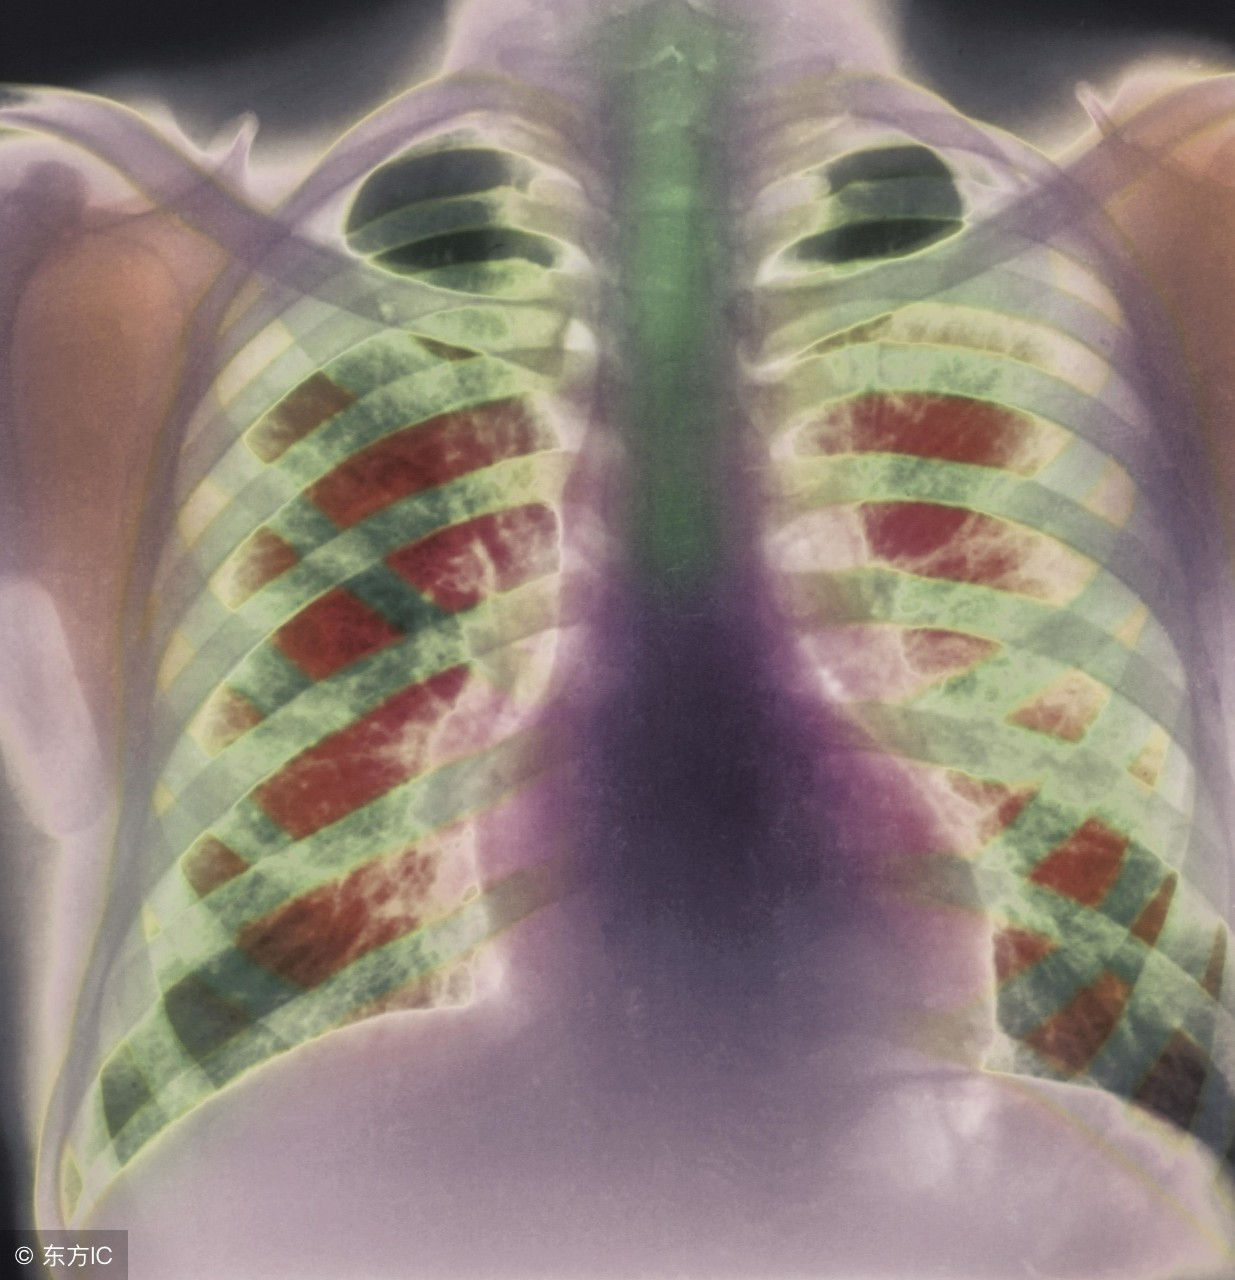

患上肺气肿的人可能会出现呼吸困难等情况,是比较棘手的一种疾病。那么患上肺气肿的话吃什么比较好呢?下面就来给大家讲讲肺气肿吃什么好,它们给你好身体哦!